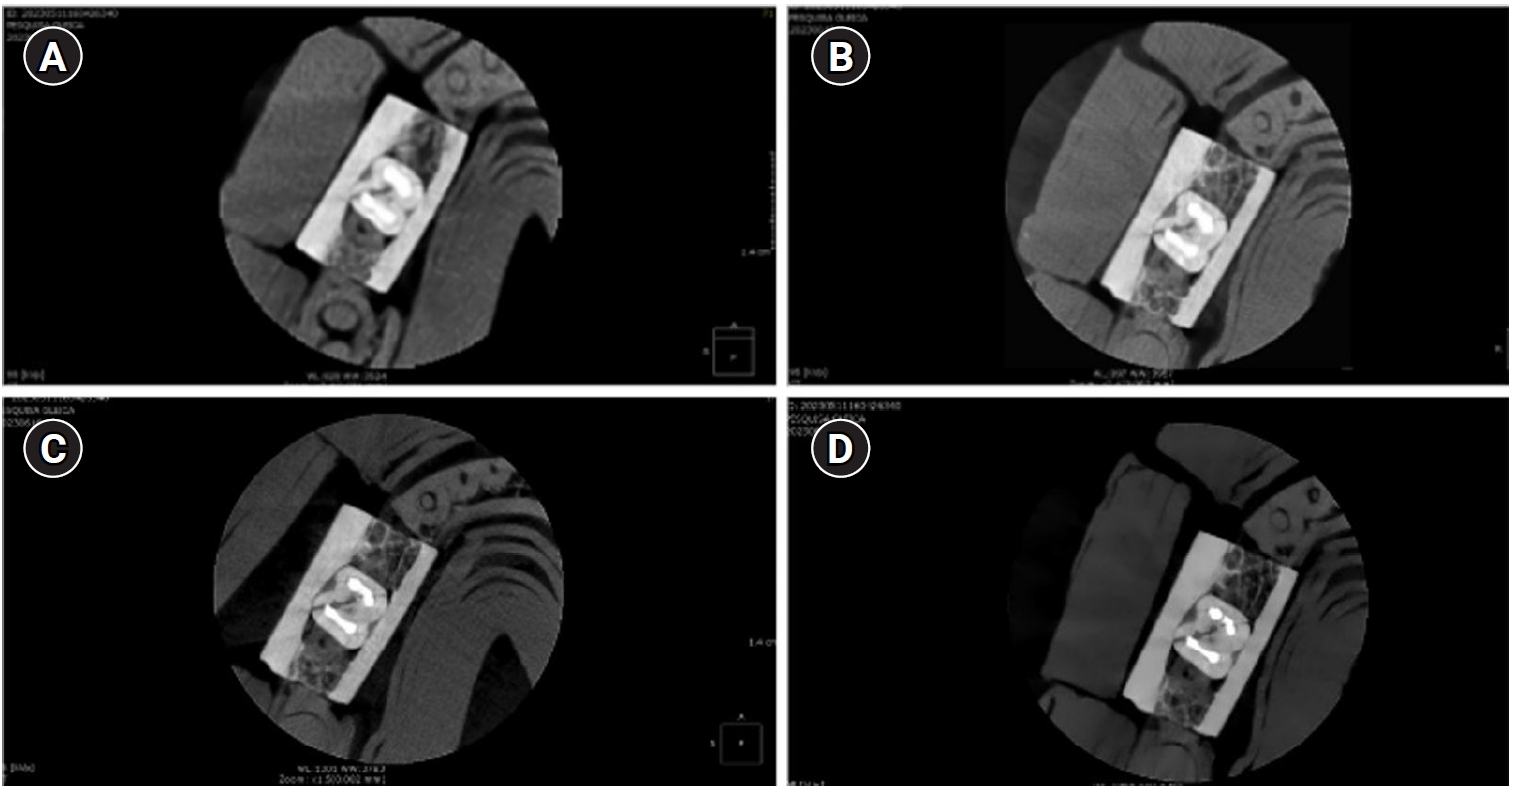

How protocol, posts, and experience affect fracture detection in multi-rooted teeth using cone-beam computed tomography: an ex vivo experimental study

Gleica Dal’ Ongaro Savegnago, Gabriela Marzullo de Abreu, Carolina Baumgratz Spiger, Lucas Machado Maracci, Wislem Miranda de Mello, Gabriela Salatino Liedke

Restor Dent Endod 2025;50(3):e23.   Published online July 24, 2025

DOI: https://doi.org/10.5395/rde.2025.50.e23

Funded: Coordination for Funding and Support of Tertiary Education

AbstractAbstract PDFPubReaderePub

Objectives

This study aimed to evaluate the influence of cone-beam computed tomography (CBCT) acquisition protocol, the presence of intraradicular metal post, and examiner experience on the detection of complete root fractures in multi-rooted teeth.

Methods

Twenty human molar teeth filled with gutta-percha were placed into artificial alveoli created in bovine ribs. The sample was divided into two groups based on the presence or absence of intraradicular posts in the distal roots. CBCT scans were obtained using four acquisition protocols with varying voxel sizes (0.28, 0.2, 0.125, and 0.80 mm). Following the creation of controlled fractures using a chisel and hammer, CBCT imaging was repeated, resulting in 160 images. Five examiners assessed the images using OnDemand software (KaVo Dental GmbH). Sensitivity, specificity, and accuracy were calculated for each examiner, CBCT protocol, and post-condition. Statistical comparisons were performed using Cochran’s Q test and McNemar test, and a significance level of 5%.

Results

In teeth without metallic posts, sensitivity, specificity, and accuracy values exceeded 0.70, 0.70, and 0.80, respectively. However, the presence of metallic posts significantly reduced diagnostic performance, particularly in low-resolution protocols evaluated by less-experienced examiners.

Conclusions

CBCT acquisition protocols should be selected based on the presence of metallic posts to optimize root fracture detection in multi-rooted teeth. Examiner experience also plays a critical role in diagnostic accuracy.